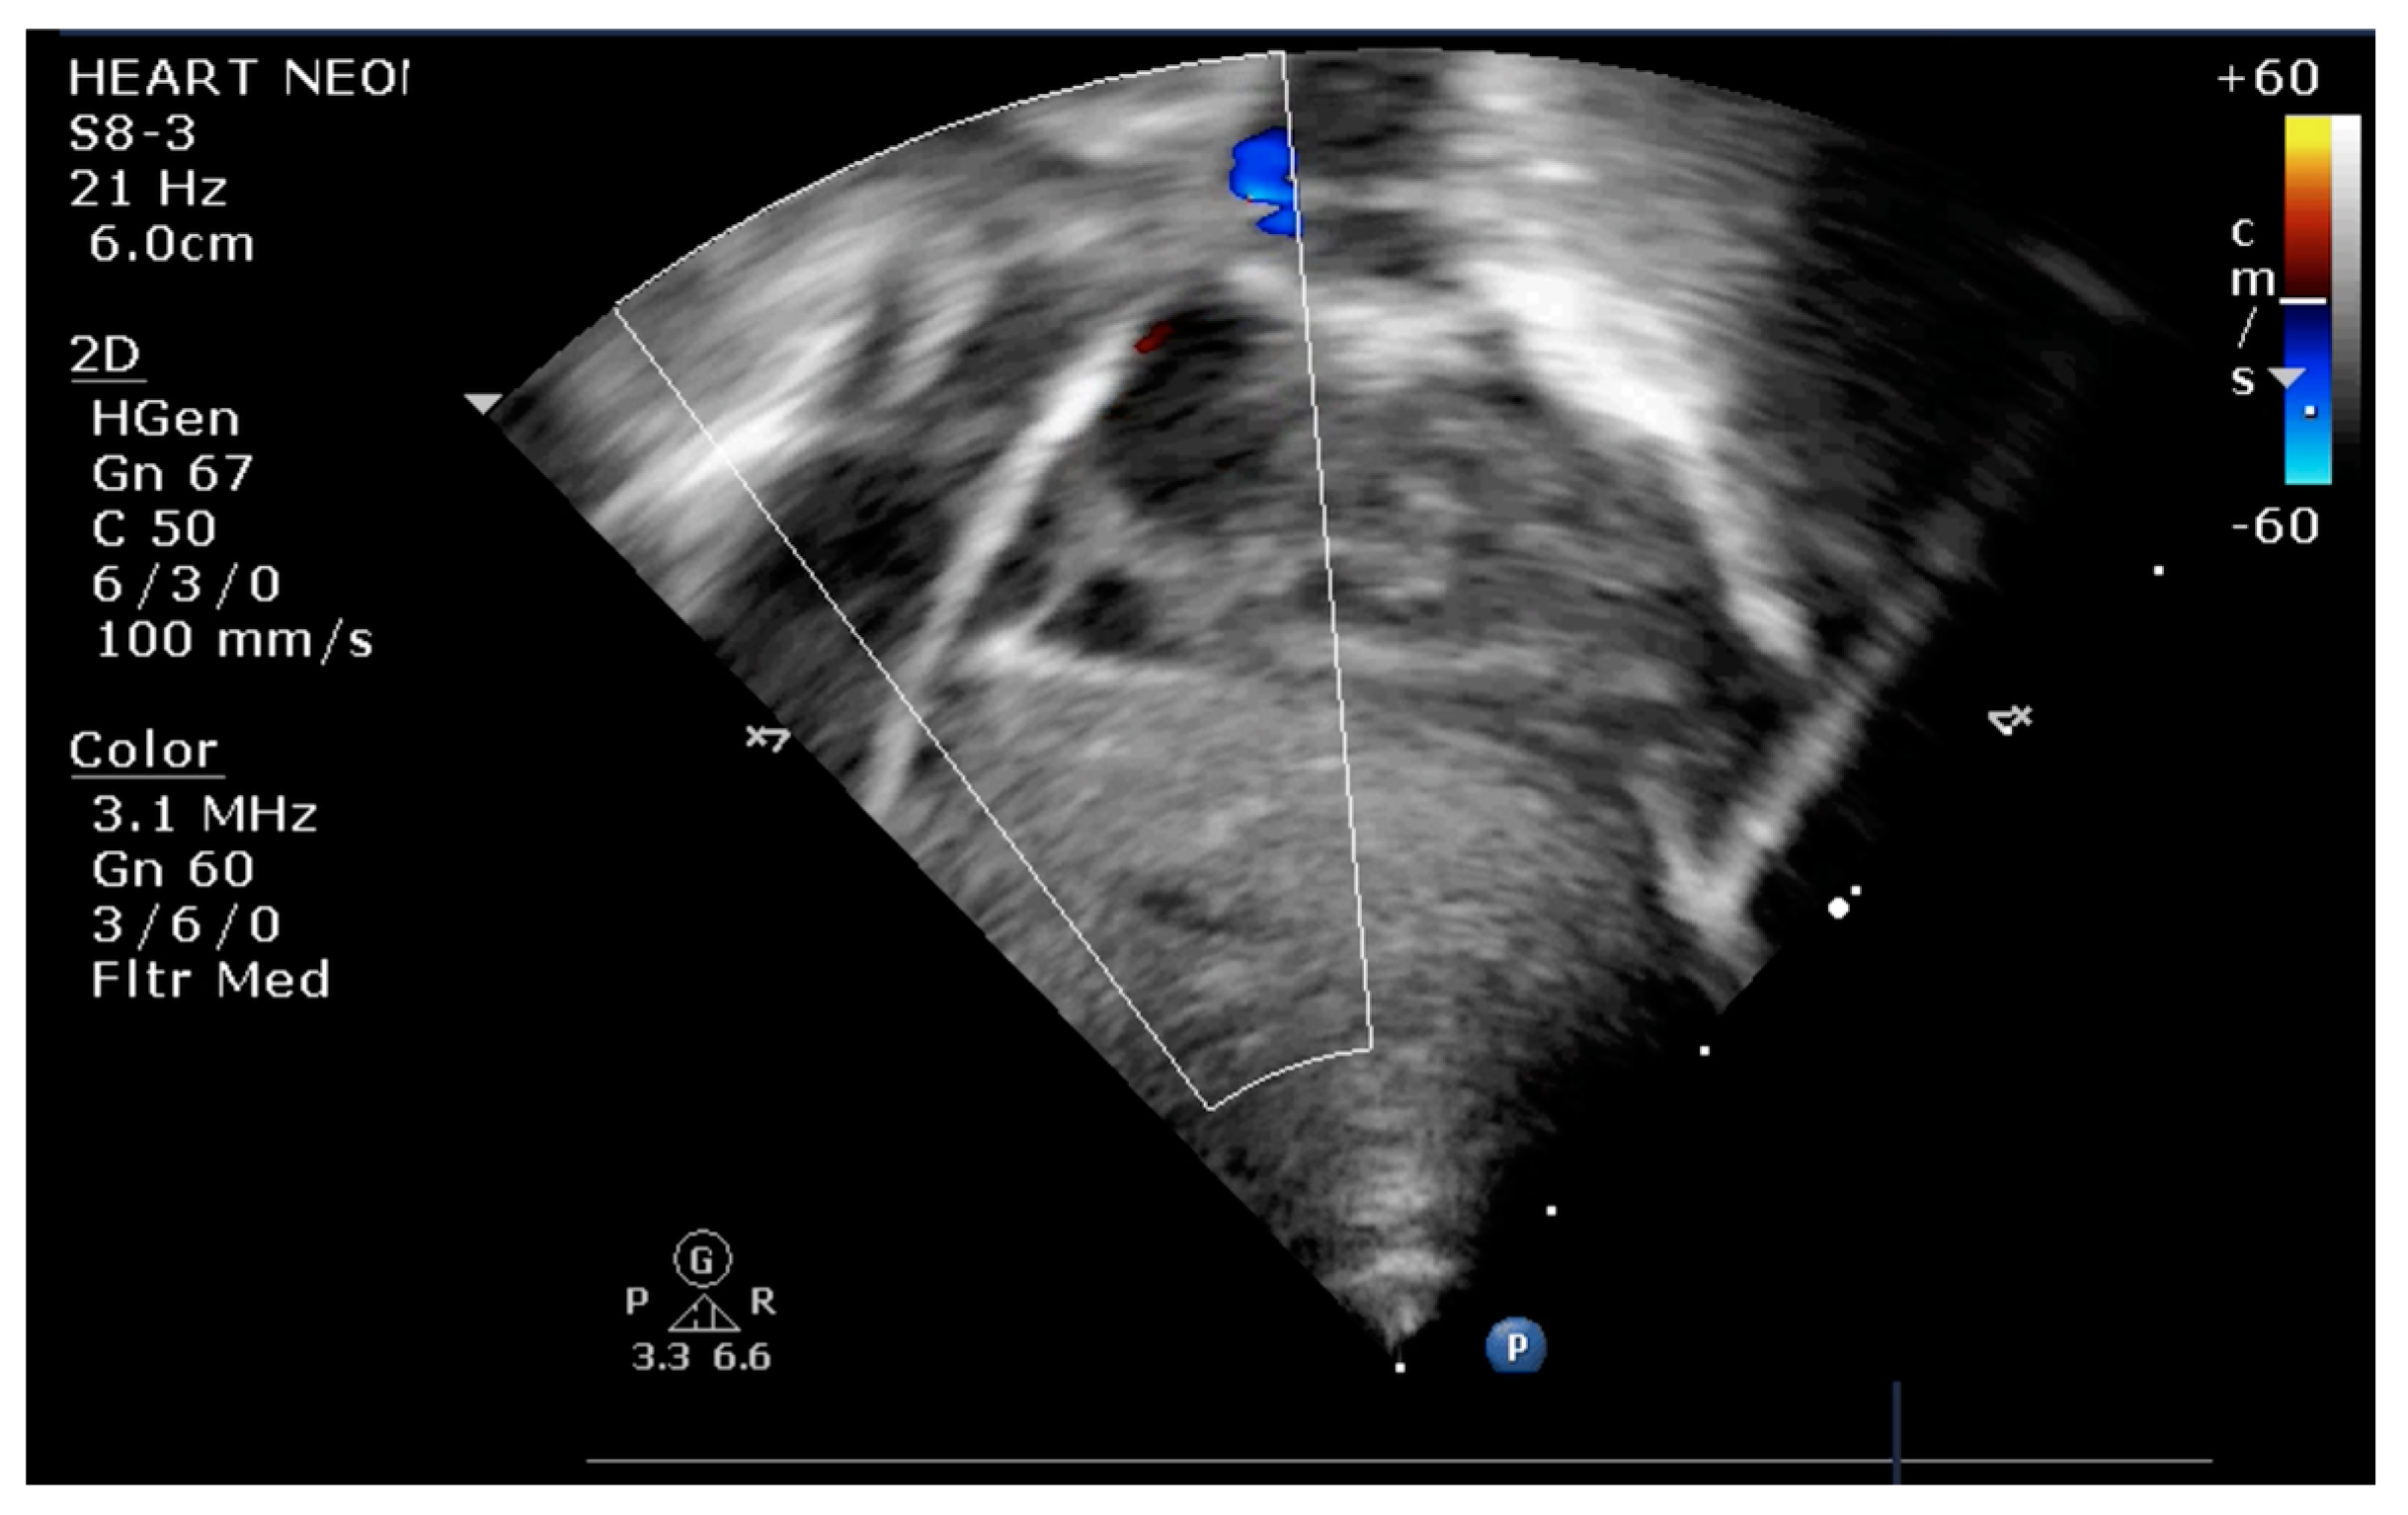

The indication for balloon atrial septostomy was made based on clinical status (low systemic arterial oxygen saturation) correlated with tissue hypoxia (persistently elevated lactate level), echocardiographic assessment (patency and size of interatrial septal defect, ductus arteriosus, and interventricular septal defect), and anticipated delay to surgery. The procedure was performed according to the institutional protocol, at the patient’s bedside, under general anesthesia, and using the Rashkind pull-back technique under echocardiographic guidance (Figure 1 and Figure 2). Vascular access was obtained via a sterile technique via the femoral or umbilical vein. The procedure was repeated several times until satisfactory atrial communication was obtained. The success of BAS was clinically objectified by increasing systemic arterial saturation by at least 10% and echocardiographically objectified by increasing interatrial communication (Figure 3).

Figure 1.

Transthoracic echocardiography (TTE) subcostal view: atrial septostomy catheter in the LA.